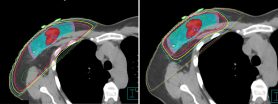

En comparación con la irradiación de mama completa, la irradiación de mama parcial tiene un campo de radiación más reducido, lo que se traduce en menos efectos tóxicos relacionados con la radiación. Por ejemplo, la irradiación de mama completa a veces causa alteraciones cosméticas o tejido cicatricial en la mama o los músculos subyacentes. Tal daño podría evitarse potencialmente con la irradiación de mama parcial, ya que se trata un volumen de tejido más pequeño.

Después de someterse a cirugía de mama conservadora y, si así lo desean, a reconstrucción oncoplástica inmediata, las pacientes reciben terapia de radiación de haz externo hipofraccionada de mama parcial. Se administra una dosis total de 35 Gy en fracciones una vez al día durante 10 días de tratamiento consecutivos (excluidos fines de semana y feriados). Las pacientes cuyos tumores se resecaron con márgenes menores de 2 mm reciben un refuerzo adicional de 9 Gy en tres fracciones. El régimen fue evaluado por el Dr. Howard Thames, Jr., Ph.D., radiobiólogo y profesor del Departamento de Bioestadística, para garantizar que la dosis fuera equivalente al régimen estándar utilizado para la irradiación de mama completa.